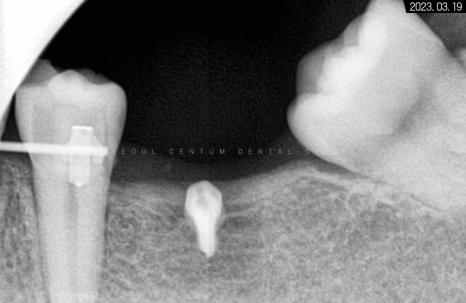

돌출감을 어느 정도 해소한 후

교합을 맞추기 전에

임플란트 과정을 시작하는 것이 좋습니다.

그래야 기간과 교합 측면에서

더 좋은 결과를 얻을 수 있습니다.

따라서 적정 시기에

CT를 촬영해 치조골 폭과 밀도를

철저하게 분석한 다음 정확한 자리를 선정하고

임플란트 식립을 진행했습니다.

하악 좌측 사랑니 발거 후

임플란트가 필요한 부분들에

픽스처를 견고하게 식립해 드렸습니다.

일정 기간이 지난 후 고정력을 체크하고

지대주에 이어서

크라운까지 예쁘게 수복해 드렸습니다~

크라운으로 감싸고 난 후의 치근단 모습입니다.

정확한 간격으로 견고하게 심어졌으며

주변 치조골 양도 풍부합니다.